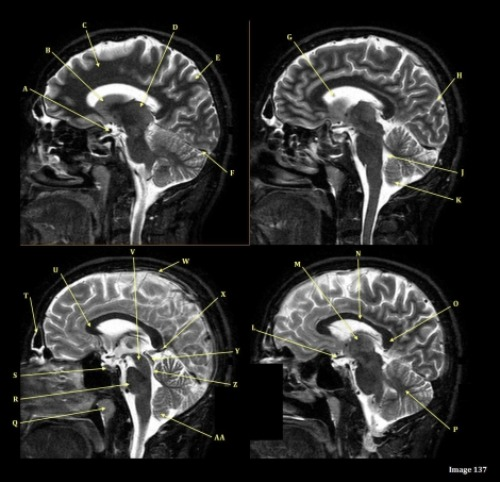

Letter A in Image 54 is pointing to:

D. Mandibular condyle

Letter C in Image 54 is pointing to:

B. Articular tubercle

Image 54 is an MRI of the ______.

C. TMJ